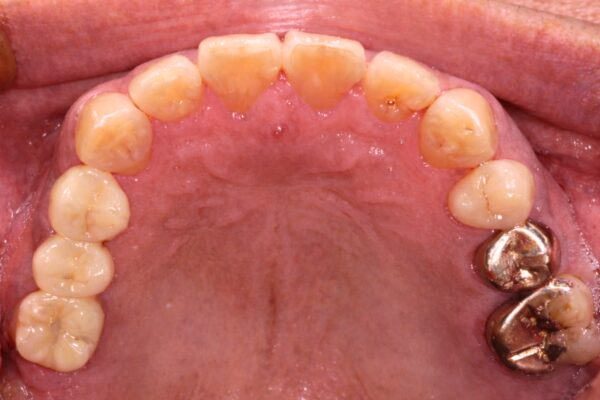

Images